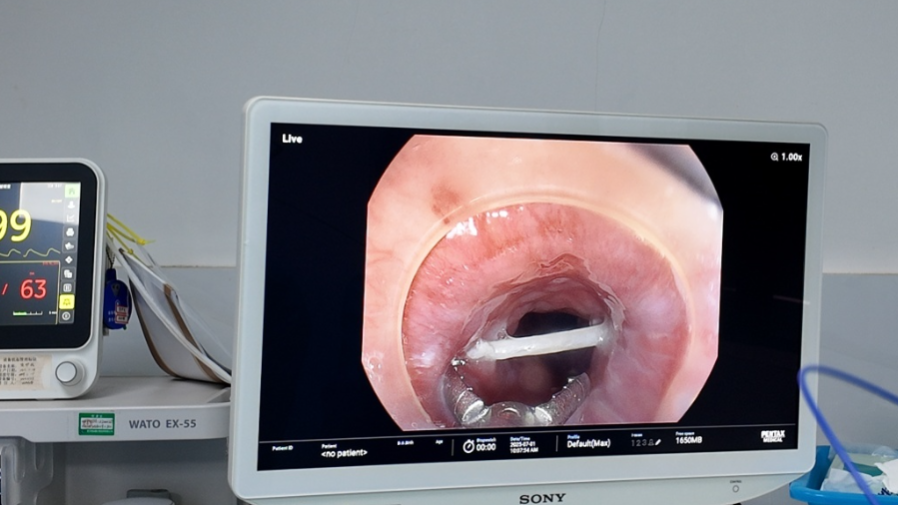

内镜下食管异物取出术

术中,内镜清晰显示一根长约3cm的鱼刺嵌顿于食管黏膜,周围组织轻度水肿。凭借精准的操作技术,医生顺利夹取异物并完整取出,手术仅耗时15分钟,未造成黏膜损伤及出血。术后患者症状即刻缓解,当天即可恢复进食,对医护团队的高效诊疗和细致照护表示由衷感谢。